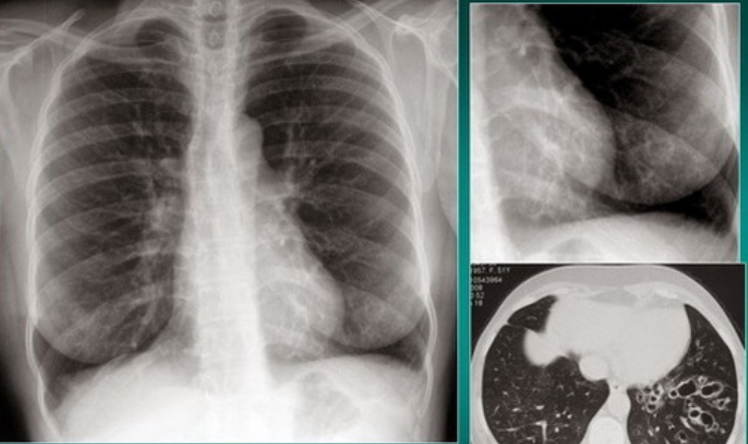

- Trên phim X quang phổi chuẩn: có thể thấy các dấu hiệu gợi ý hoặc khẳng định chẩn đoán giãn phế quản trong một số trường hợp giãn phế quản nhiều và nặng. Tuy nhiên chẩn đoán xác định giãn phế quản thường phải dựa vào phim chụp cắt lớp vi tính lớp 1mm, độ phân giải cao

Hình ảnh giãn phế quản trên X quang:

- Thành phế quản tạo thành các đường song song (đường ray).

- Thể tích của thuỳ phổi có giãn phế quản nhỏ lại, các đường mờ mạch máu phổi xít lại với nhau nếu có xẹp phổi.

- Có các ổ sáng nhỏ giống hình ảnh tổ ong, có thể có ổ sáng với mực nước ngang kích thước thường không quá 2 cm

- Hình ảnh viêm phổi tái diễn vào mùa lạnh xung quanh khu vực giãn phế quản.

- Các đám mờ hình ống biểu hiện của các phế quản bị lấp đầy chất nhầy, mủ.

- Khoảng 7 - 30% trường hợp chụp phổi chuẩn không thấy gì bất thường.

- Chụp cắt lớp vi tính vi tính lớp mỏng, độ phân giải cao: là tiêu chuẩn vàng trong chẩn đoán xác định giãn phế quản. Các dấu hiệu có thể gặp:

- Đường kính trong của phế quản lớn hơn động mạch đi kèm.

- Các phế quản không nhỏ dần được quy định khi phế quản trên một đoạn dài 2 cm có đường kính tương tự phế quản đã phân chia ra phế quản đó.

- Thấy phế quản ở cách màng phổi thành ngực dưới 1 cm.

- Thấy phế quản đi sát vào màng phổi trung thất.